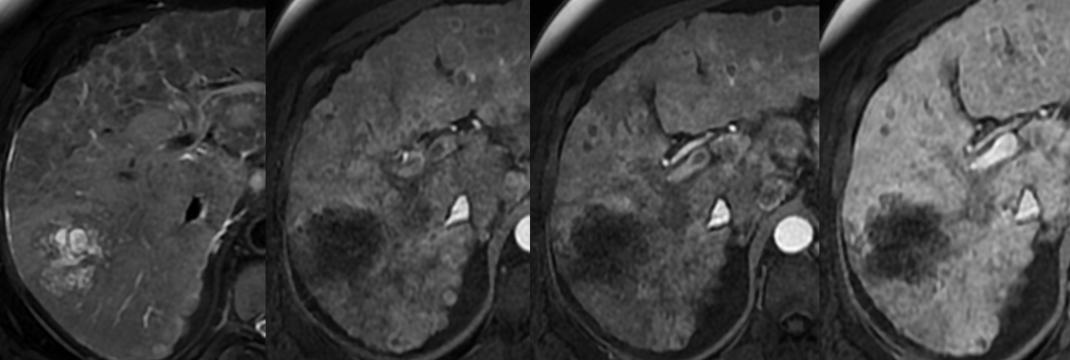

CT

- Natif = hypodense

- Artérielle = prise de contraste périphérique non discontinue

- Portal = peut être remplie ou avoir un washout périphérique

- Tardive = Prise de contraste persistante (tissus fibreux)

- Rétraction capsulaire

- Lésions satellites fréquentes

IRM

- T1 FS: Plus hypo que le parenchyme pancréatqiue

- T2 Hyper-périphérique (viable) et hypo- central (fibrose)

- T1 gd1+ : Meilleure détection des petits CholangioK que le CT